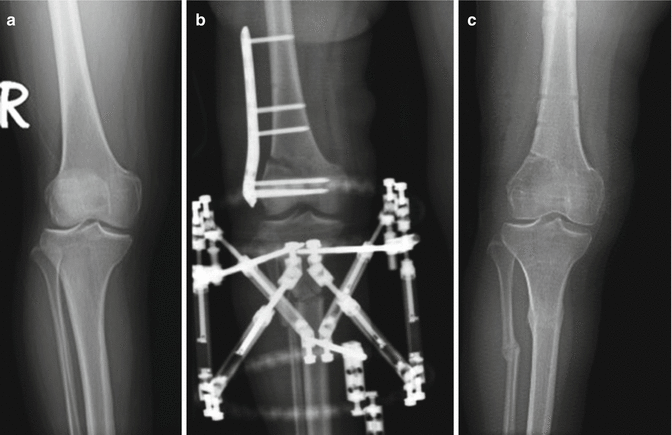

Fig. 27.2

X-rays of the same patient. The malalignment in the limb was corrected simultaneously (a) Preoperative x-ray, (b) X-ray showing the femoral and the tibial osteotomies, (c) X-ray at the time of second-look arthroscopy